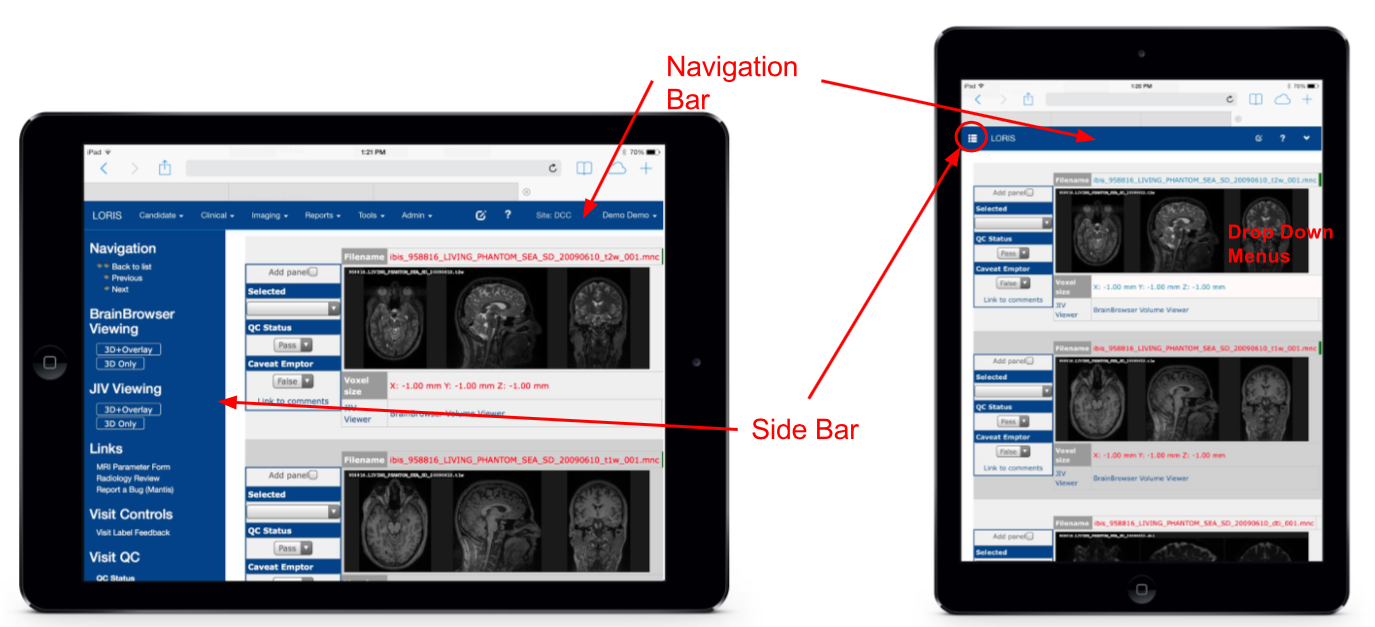

Imaging Browser

Imaging Quality Control

BrainBrowser

..a set of web-based 3D visualization tools primarily used for viewing neurological data i.e. MRI scans.

It allows for real-time manipulation and analysis of 3D neuroimaging data through any modern web browser. TRY ME!

Mobile - Imaging